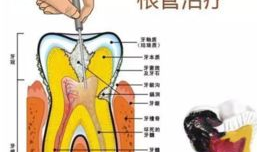

根管治疗视频,从视频学习根管治疗技巧与流程

最近是不是牙齿疼得你坐立不安,连笑容都变得苦涩了呢?别担心,今天就来给你揭秘一下那个听起来有点吓人的根管治疗,让你对这个过程有个...